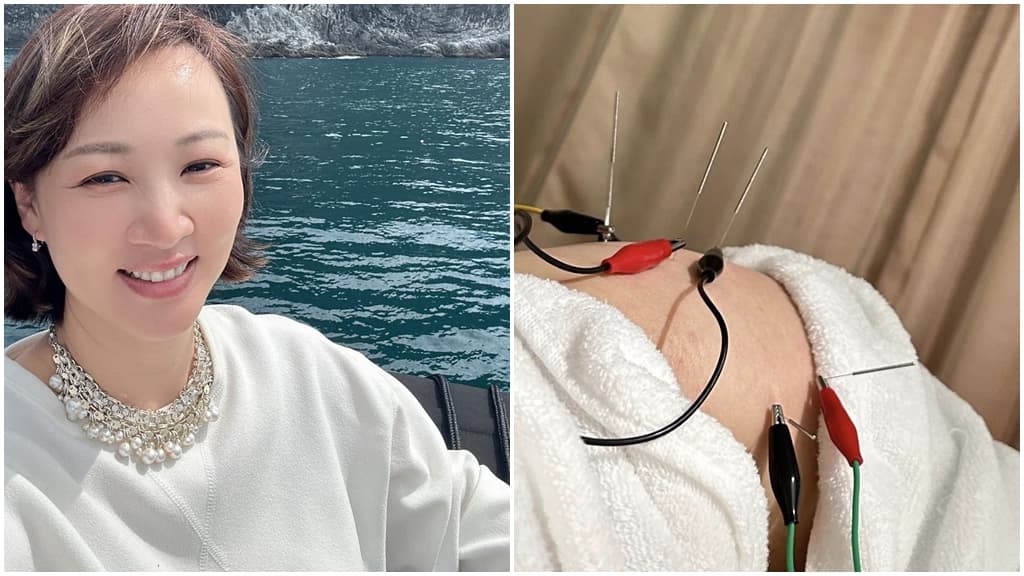

活躍日本歌壇逾30年的搖滾樂團「THE YELLOW MONKEY」主唱吉井和哉驚傳罹癌,57歲的他透過官網公開罹患喉頭癌的消息。據了解他去年因為發炎發現喉頭息肉,去年2月切除息肉後一直不滿意歌唱水準,9月和10月分別再切除息肉,11月發現早期喉頭癌。醫師表示,喉頭癌在咽喉癌中算幸運的,因為病灶侷限在喉返軟骨內,早期發現不易轉移,但要戒菸酒並每個月追蹤,避免復發。

吉井和哉3度切除聲帶息肉 後發現早期喉癌

吉井和哉表示,他前年12月結束武道館個別演唱後就感覺不適,分別在去年2月、9月和10月進行3次切除手術,經過戒聲期開始練唱時,他發現喉嚨疑似長腫瘤,11月醫師確認為早期喉頭癌。醫師說明治療3個月可根治,他也馬上接受治療,今年初已經順利根治。他很開心能早期發現腫瘤,但因為認為聲音尚未回復可以上台表演的水準,因而取消年底的演唱。

▲吉井和哉在官網上公開罹癌和治療經過,並取消年底的單飛20周年演唱會。(圖片/翻攝自吉戒和哉Twitter)